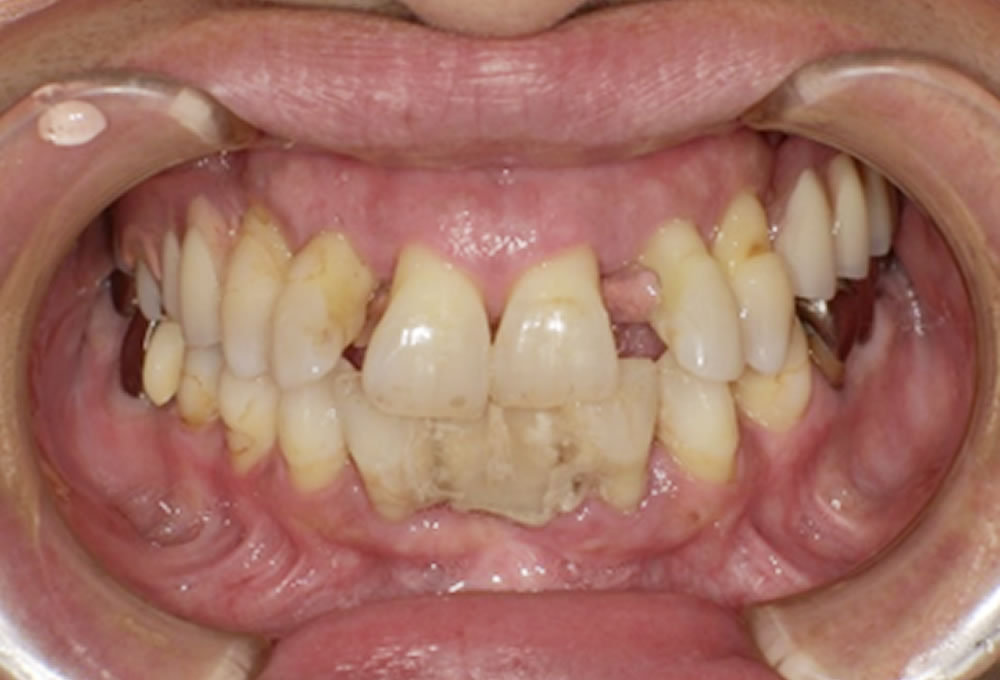

治療後の変化

治療後は、左右どちらでも安定して噛めるようになり、食事の際の不安が大きく軽減されました。

今回のケースは、悩みながらも入れ歯相談を受けていただけたことが、良い結果につながったかと思います。

入れ歯に対して不安や抵抗感をお持ちの方も多いですが、しっかりと設計された義歯を選ぶことで、「噛める」「見た目が自然」「歯を守れる」治療が可能になります。入れ歯相談を受けられた方の満足度は非常に高く、今後も継続して力を入れていきたいと考えています。